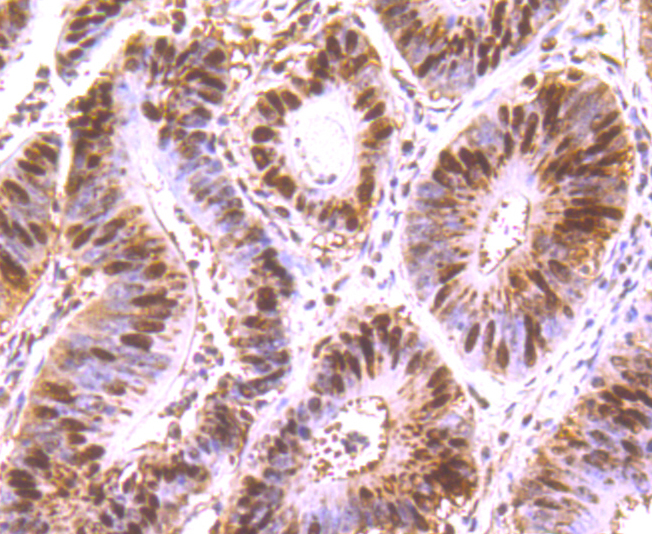

IHC: 1:100-1:500

文献和实验:使用 Anti-phospho-Akt (Ser473) Rabbit mAb 对石蜡包埋的人乳腺癌组织进行免疫组织化学分析。(图 A)使用免疫组化试剂盒M&R HRP/DAB Detection IHC Kit,抗体 1:100 稀释;(图 B) 采用普通免疫组化试剂盒,抗体 1:25 稀释。 图 6 免疫组化实验检测 Erk1/2 表达 注:使用 Anti-Erk1/2 Mouse mAb与p44/42 MAPK (Erk1/2)Rabbit mAb 对正常小鼠心脏组织进行免疫